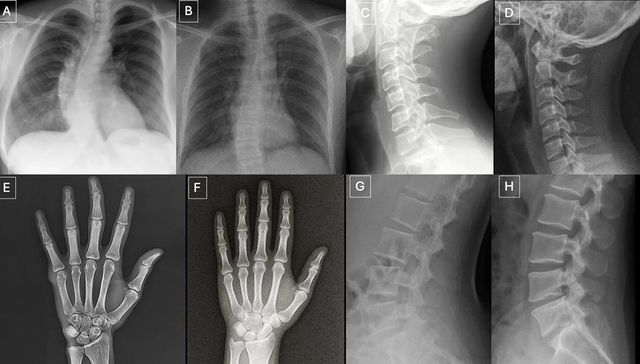

Radiografías deepfake preocupan a los médicos: ni los humanos ni la IA las distinguen

27.03.2026 09:07